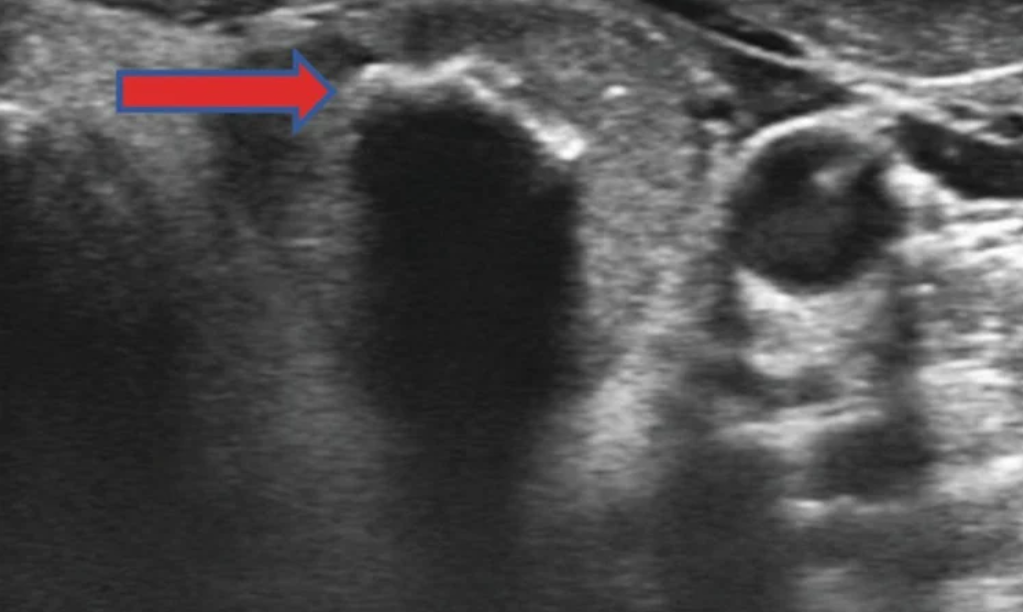

Cần phân biệt kết quả siêu âm phát hiện các vi vôi hóa hay là vôi hóa lớn? Một trong những đặc điểm siêu âm quan trọng nhất gợi ư ung thư là sự hiện diện của các vi vôi hóa, được nh́n thấy dưới dạng các điểm sáng nhỏ có kích thước ≤ 1 mm, xuất hiện trên ảnh siêu âm tuyến giáp.

Do đó, khi có mặt trên siêu âm, vi vôi hóa đại diện cho vùng ung thư tuyến giáp thể nhú. Ngược lại, vôi hóa lớn là những mảng canxi lớn, với kích thước > 1 mm (có thể đến 5-10 mm) có thể xuất hiện bên trong nhân giáp hoặc ở ngoại vi của nhân (gọi là vôi hóa dạng vỏ trứng/ vành), thường được nh́n thấy dưới dạng các điểm sáng lớn trên siêu âm.